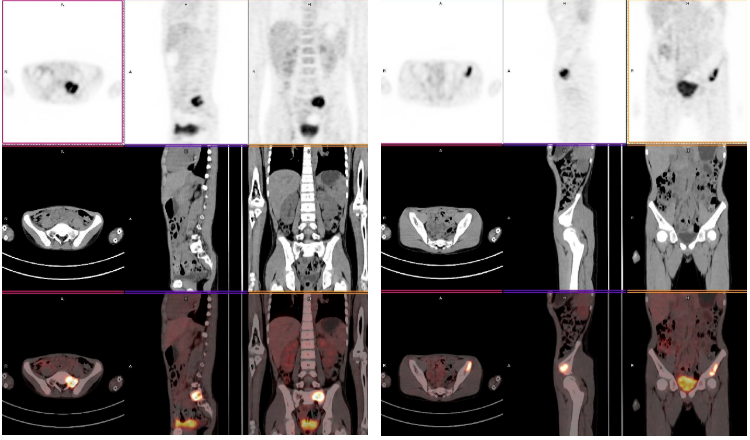

为了全面评估病情、明确全身状况并指导后续治疗,小希来到南京全景医学影像中心,接受了全身 PET/CT 检查。

全身 PET/CT 显像示:

(1)左侧咽外侧间隙、左颈部胸锁乳突肌前内侧多发 FDG 异常高摄取融合肿大淋巴结,以左颈部胸锁乳突肌前内侧为著;

(2)右侧第 6 侧肋、骶 1 椎体左侧部、左侧髂骨体、右侧髋臼及双侧股骨中段骨髓部位多发局限性 FDG 异常高摄取病灶,以右侧股骨中段髓腔内为著;

(3)全身其余部位未见明显异常高摄取典型恶性淋巴瘤浸润征象。

综合病史以及 PET/CT 影像所见,符合侵袭性淋巴瘤多部位浸润(IV 期,Lugano 分期标准)FDG-PET/CT 影像表现,肿瘤负荷较大位于左颈部胸锁乳突肌前内侧,影像生物学特点符合成熟 B 细胞淋巴瘤。